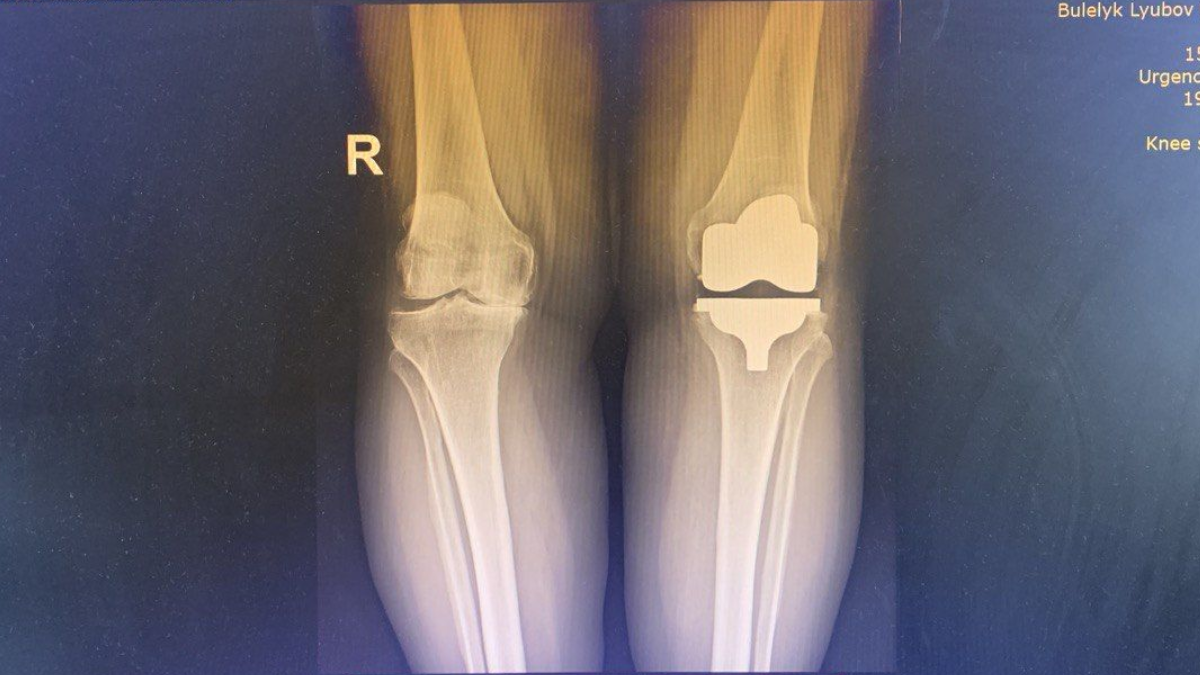

Однією з пацієнток, яку оперували зі застосуванням кінематичного методу, стала Любов Булелик із села Заріччя Делятинської громади. Жінка розповідає, що проблеми з колінами тривали роками, однак значно посилилися після коронавірусу.

У 2023 році їй підтвердили виражений артроз і рекомендували операцію. Пізніше виявлена онкологія ускладнила ситуацію. Після операції жінка пройшла курс хіміотерапії, променевої та гормонотерапії. Після гормонотерапії стан колін різко погіршився.

«Це мене так зловило, що я просто не могла вже ні ходити, ні згинати, на милицях сюди прийшла. І Андрій Іванович каже: треба оперувати. Я кажу, як треба, то я готова, бо дальше вже не можу, це вже все, фініш. Та й прооперували, я дуже задоволена», — розповідає Любов Булелик.

За словами хірурга, без оперативного втручання пацієнтка не змогла б ходити. Зараз вона успішно проходить реабілітацію: займається на доріжці, велотренажері, проходить процедури пасивного згинання й розгинання: